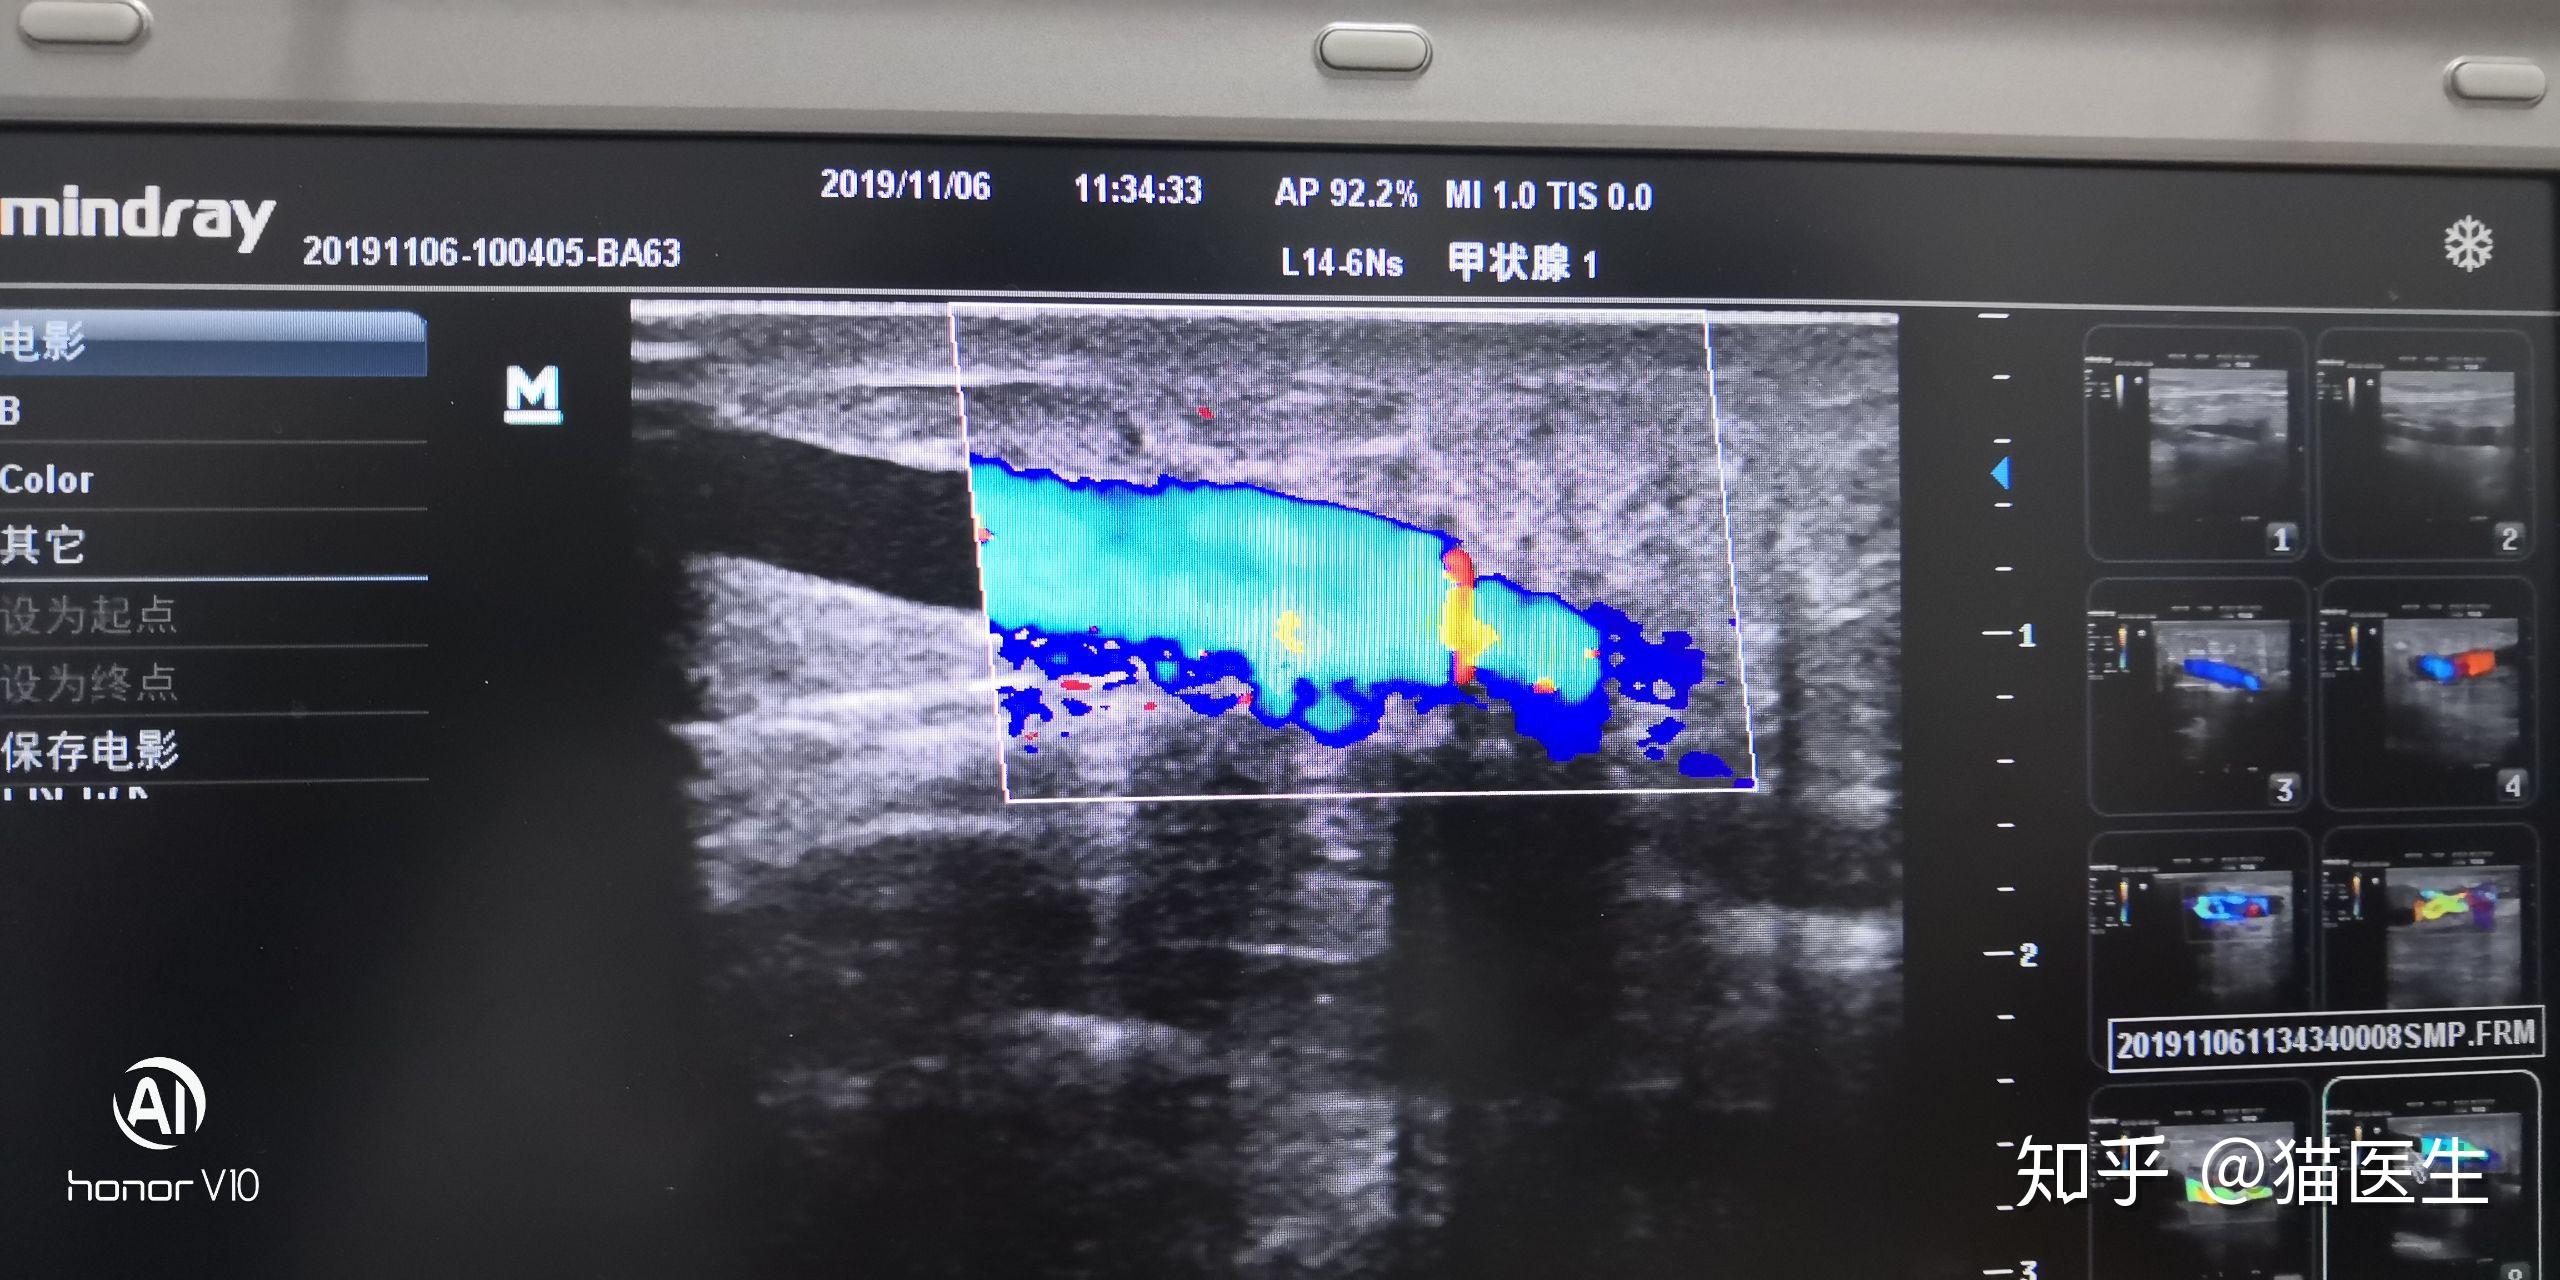

彩超引导下穿刺左侧头静脉